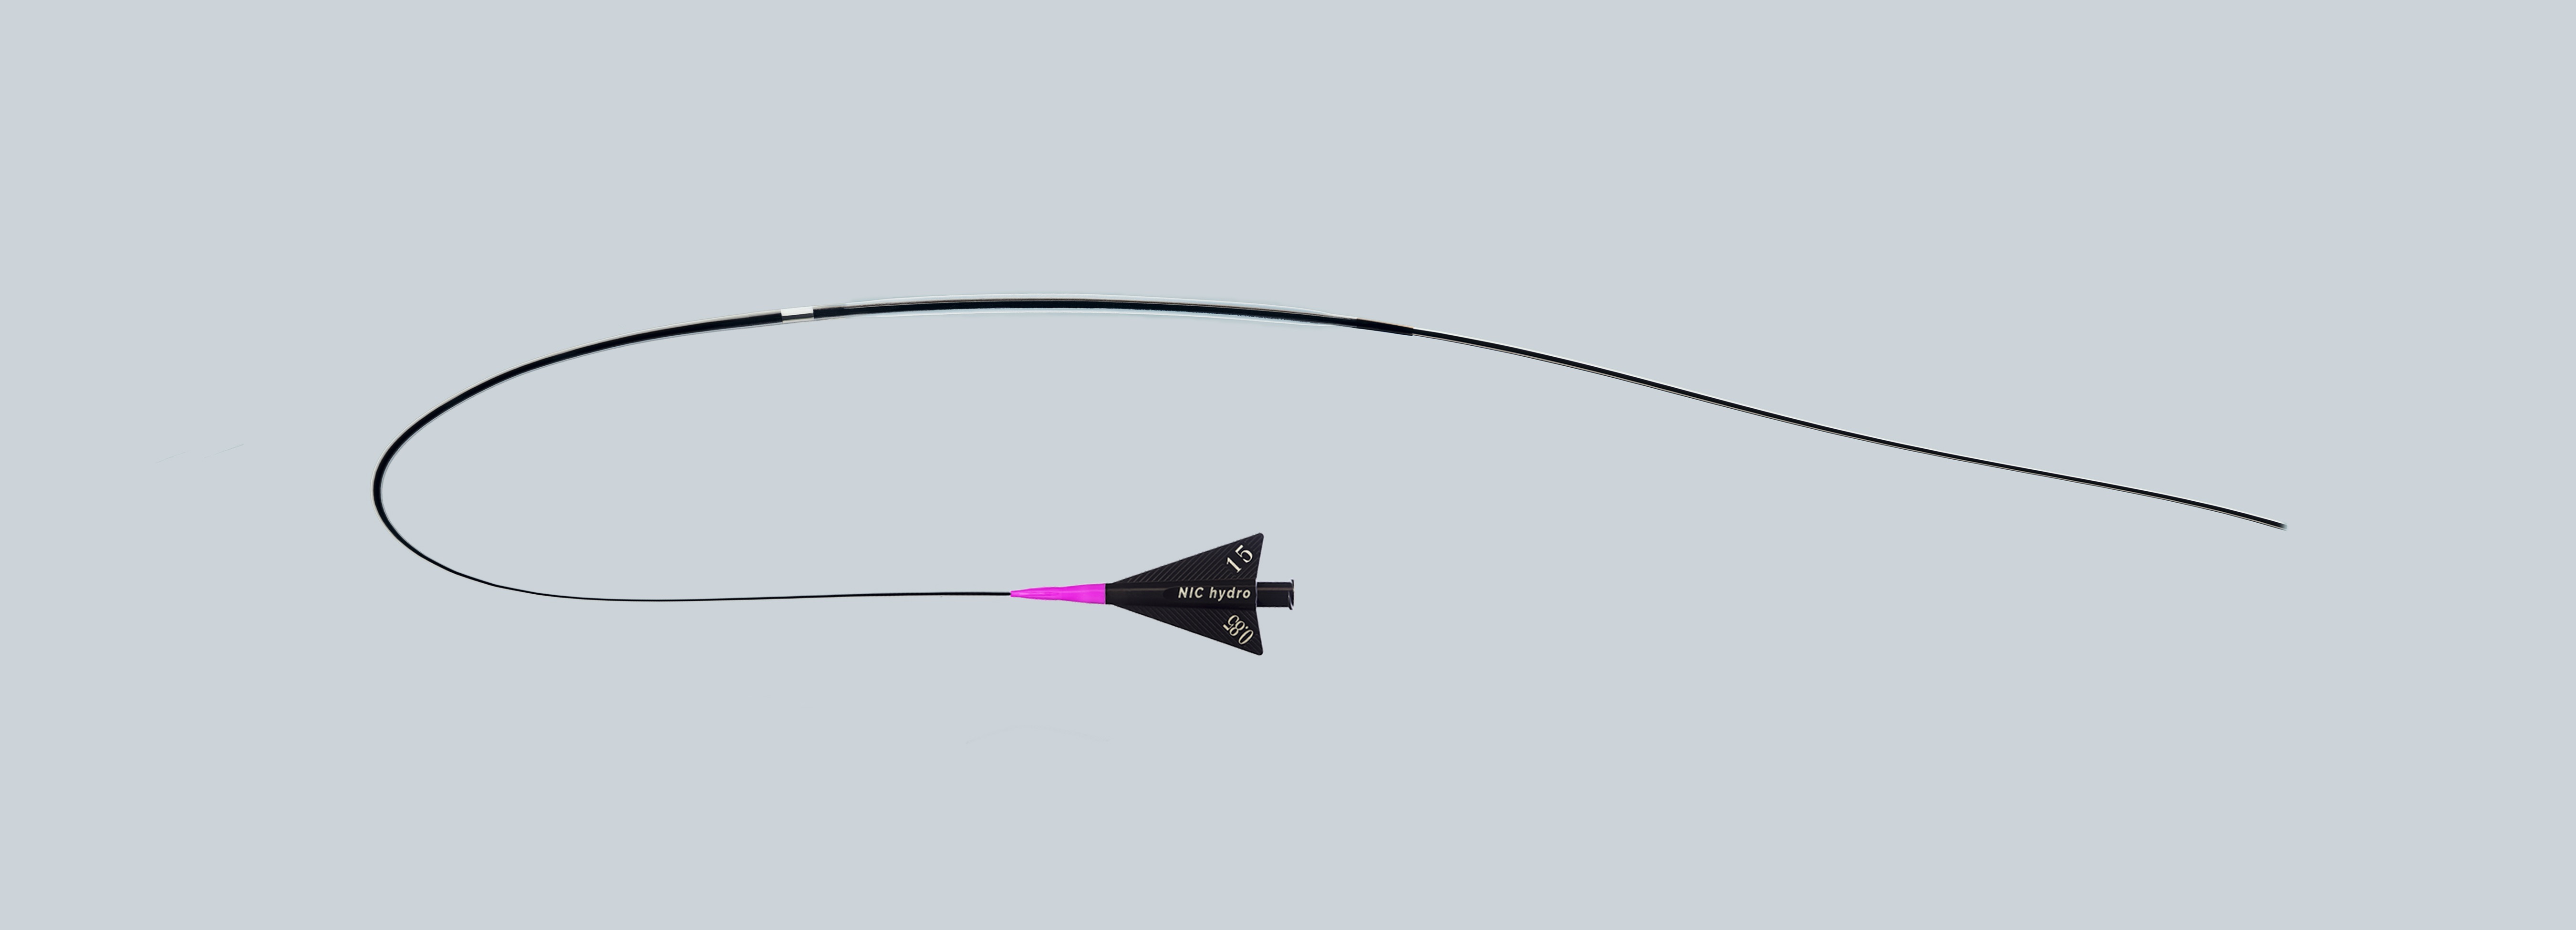

SIS Medical, founded in 2007 is a Swiss based medical company dedicated to the development, production and distribution of innovative very high performance PTCA balloon catheters which is specifically designed to extend treatment options. They manufacture high and super high pressure PTCA balloons for targeting unmet clinical needs with regular PTCA balloons such as undilatable lesions and in-stent restenosis.